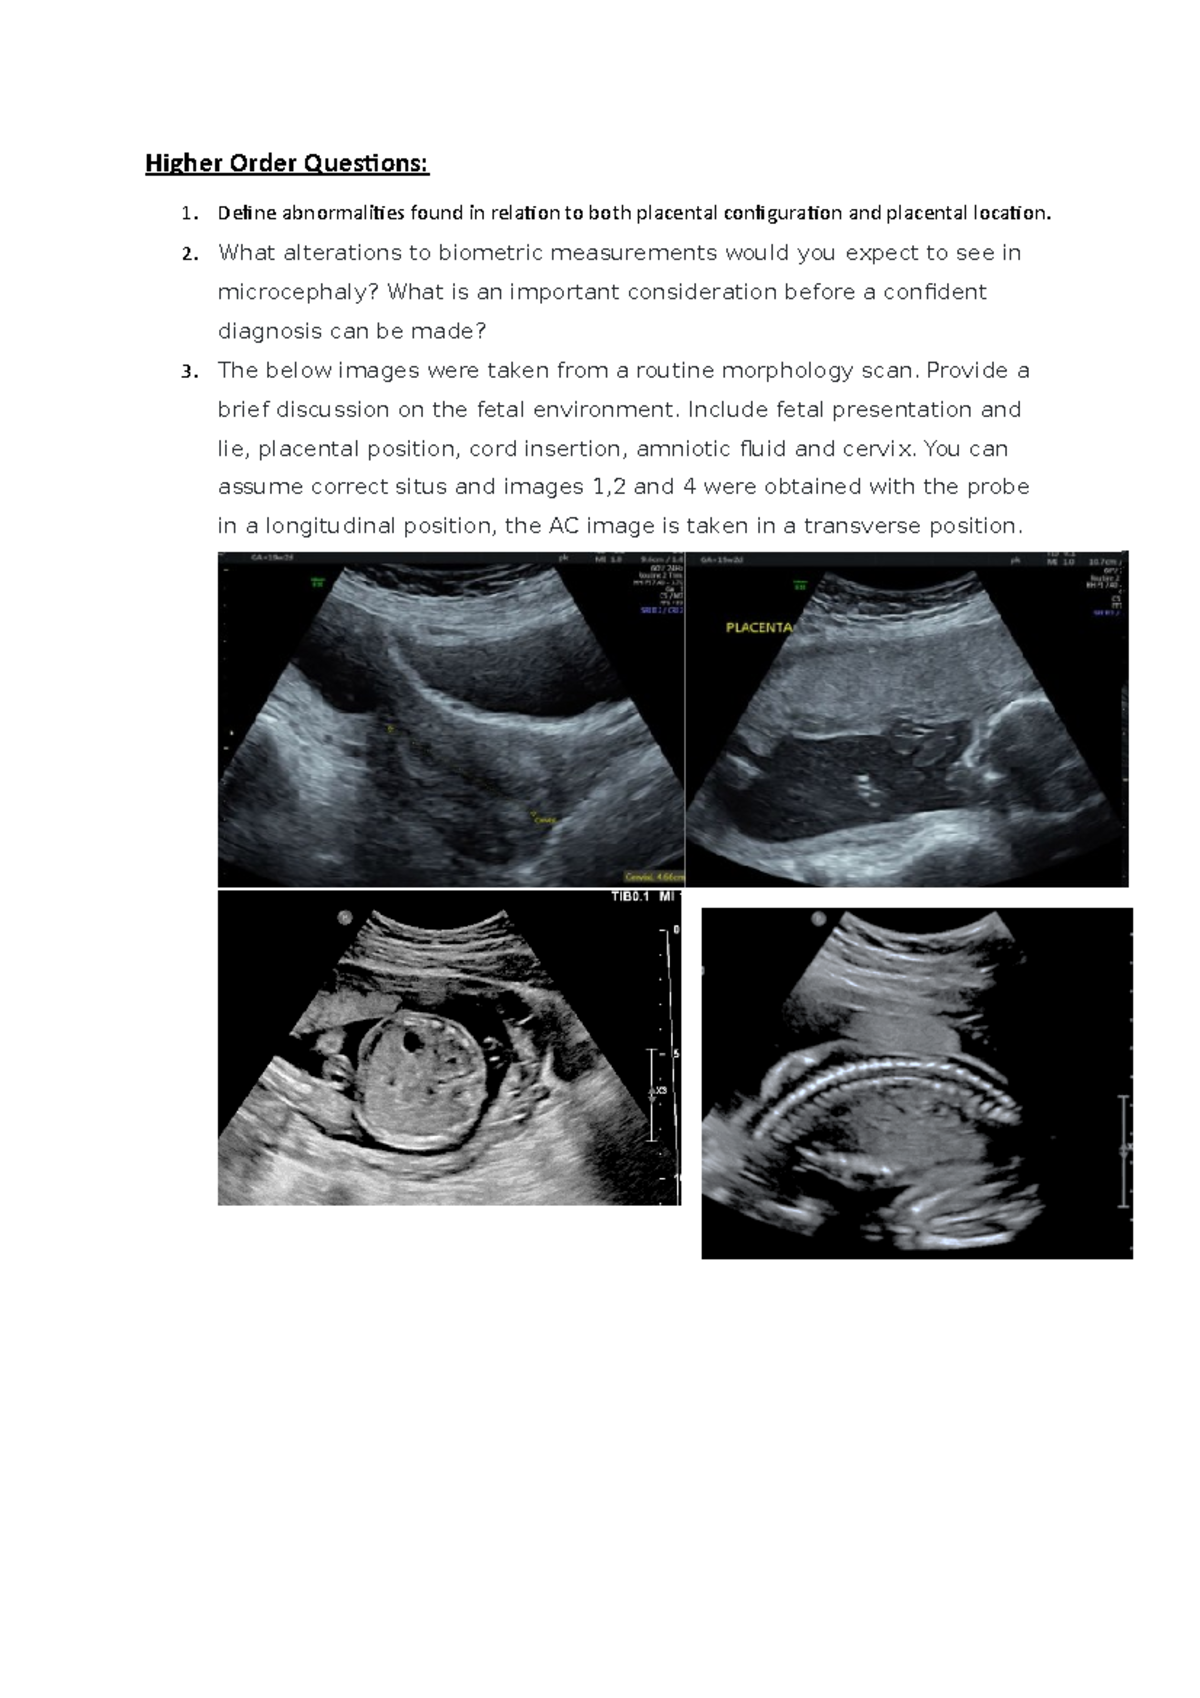

Higher Order Questionsenvironment,biometry, and heart Higher Order Biometry Questions Make an educated guess of whether the sample mean and sample standard deviation for the 14 observations would increase, decrease, or. Asked a question related to biometry when comparing cell densities of the same sample across multiple machines, what method could i use to evaluate variation?. Biometry, also called biostatistics or biometrics, is the application of statistics and other mathematical. Biometry Questions.